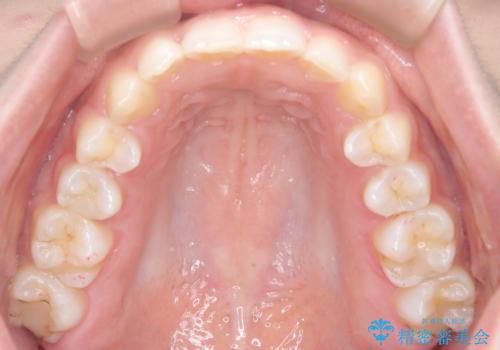

- 患者様は、ディープバイト(深い噛み合わせ)と、咬合平面の左下がりが気になるとのことでご来院されました。診断の結果、非抜歯で治療可能と判断し、透明なマウスピース型矯正装置「インビザライン」を用いる方針としました。治療では、歯列全体の調整を行いながら、咬合平面の水平化を重点的に進める計画を立案しました。2年間で計画的にマウスピースを交換し、左右のバランスと噛み合わせの改善を目指しました。

ディープバイトの矯正は、噛み合わせが深くなりがちなため、細心の注意を払いながら進める必要があります。本症例では、奥歯の高さを調整しつつ前歯の噛み合わせを浅くすることで、全体の咬合バランスを整えました。また、咬合平面の左下がりを修正する過程で、歯列に不均等な力がかからないよう、インビザラインのアタッチメント配置を最適化しました。患者様には装着時間を守っていただき、治療が計画通り進むよう協力をお願いしました。治療終了後には、リテーナーを装着して安定性を確保しました。